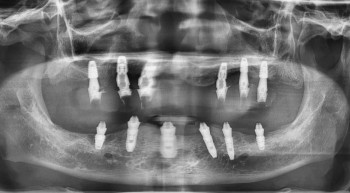

전체 임플란트 수술 케이스 전/후 사진

멀티플 임플란트 시술